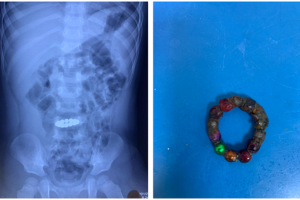

Mùng 6 tết, bệnh viện Nhi đồng Thành phố tiếp nhận trẻ L. T. Q. 26 tháng tuổi, nam, ngụ ở Đồng Tháp trong tình trạng bứt rứt, khó chịu, đau bụng, ói. Khai thác...